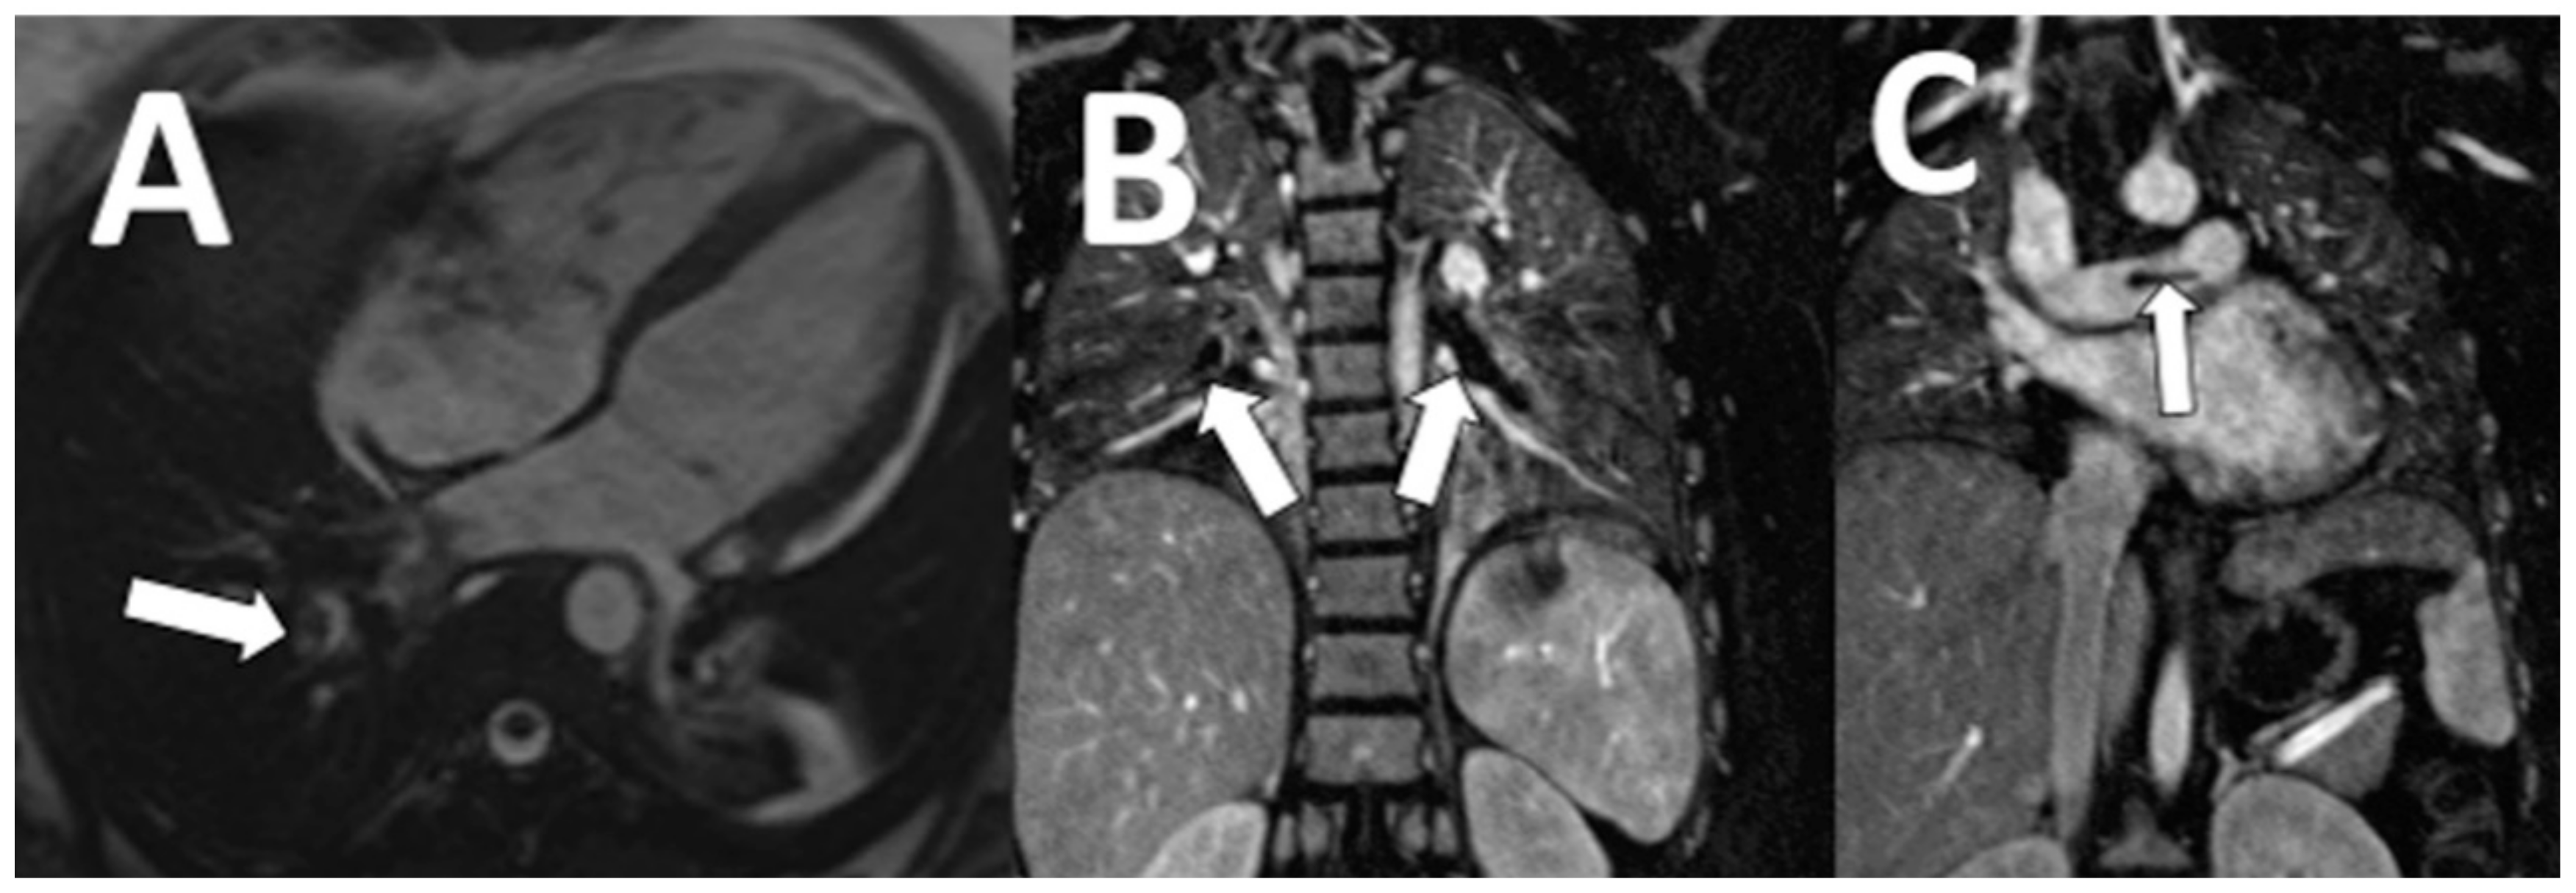

| Clinically significant NCA (n = 25) | |

| Aortic dissection | 2 (8) |

| Aortic aneurysm | 3 (12) |